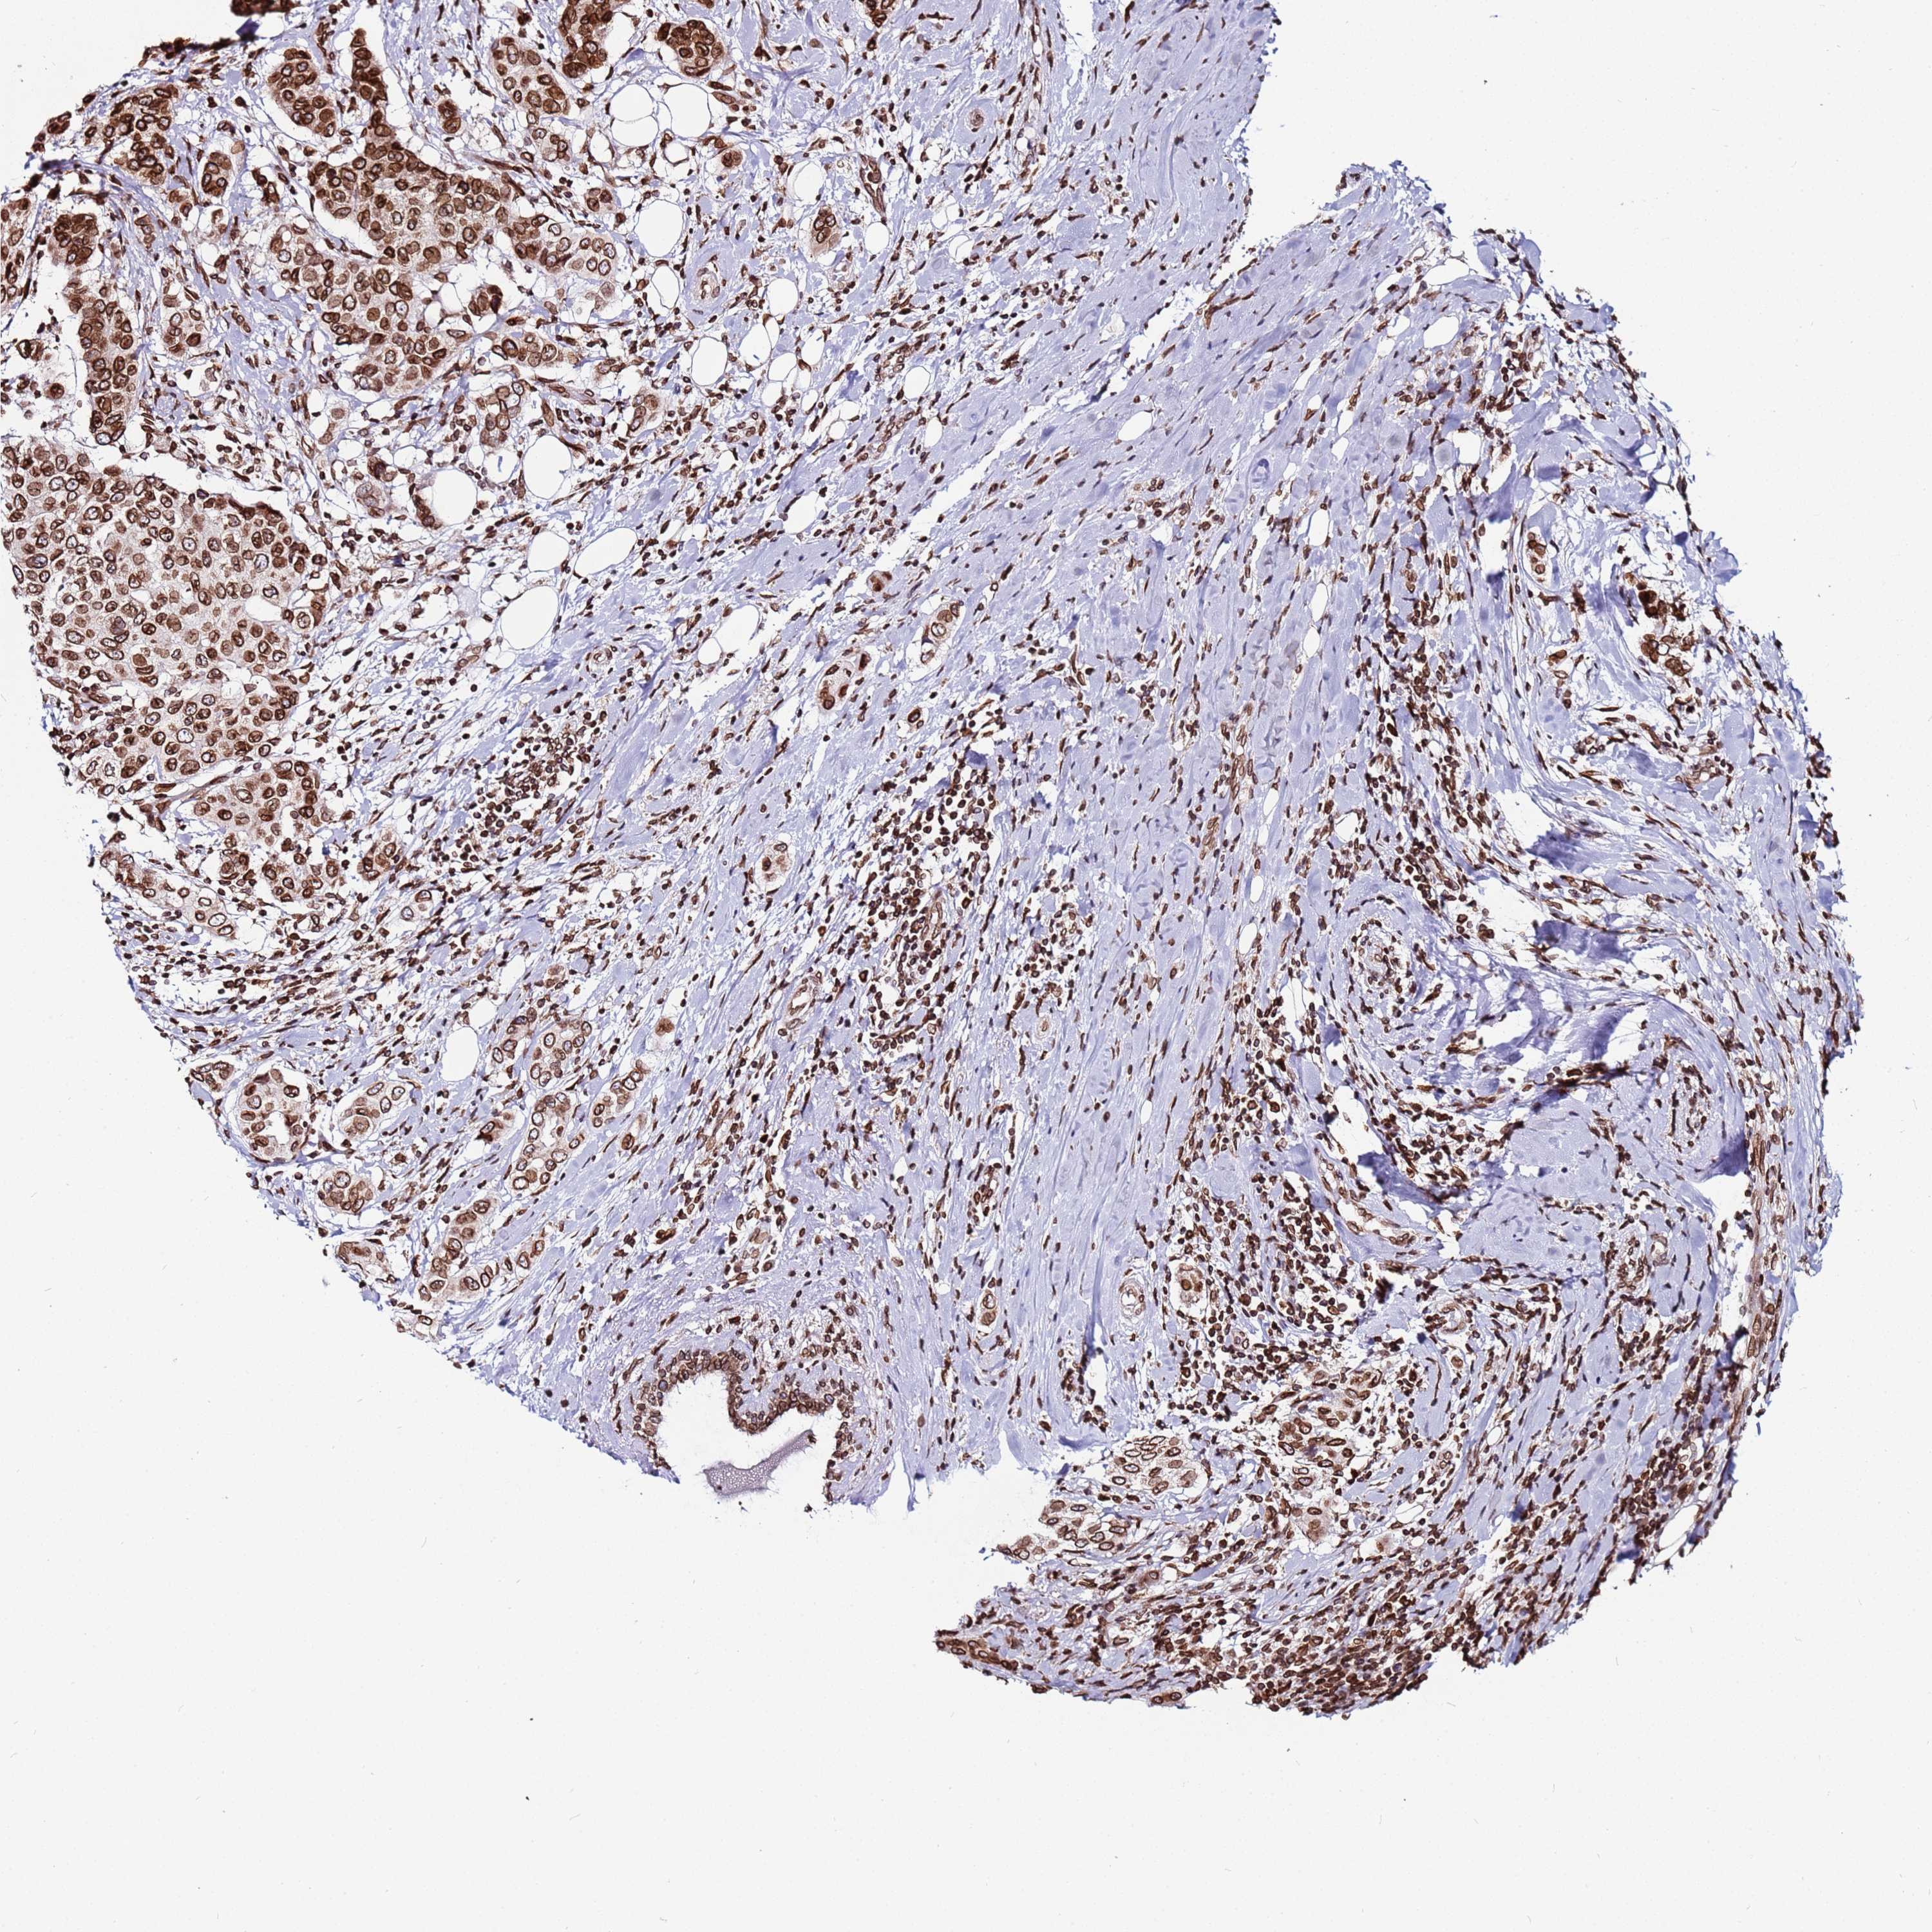

BRCA TCGA BRCA VALIDATION PROTEIN EXPRESSION

ANTIBODIES

AND

VALIDATION